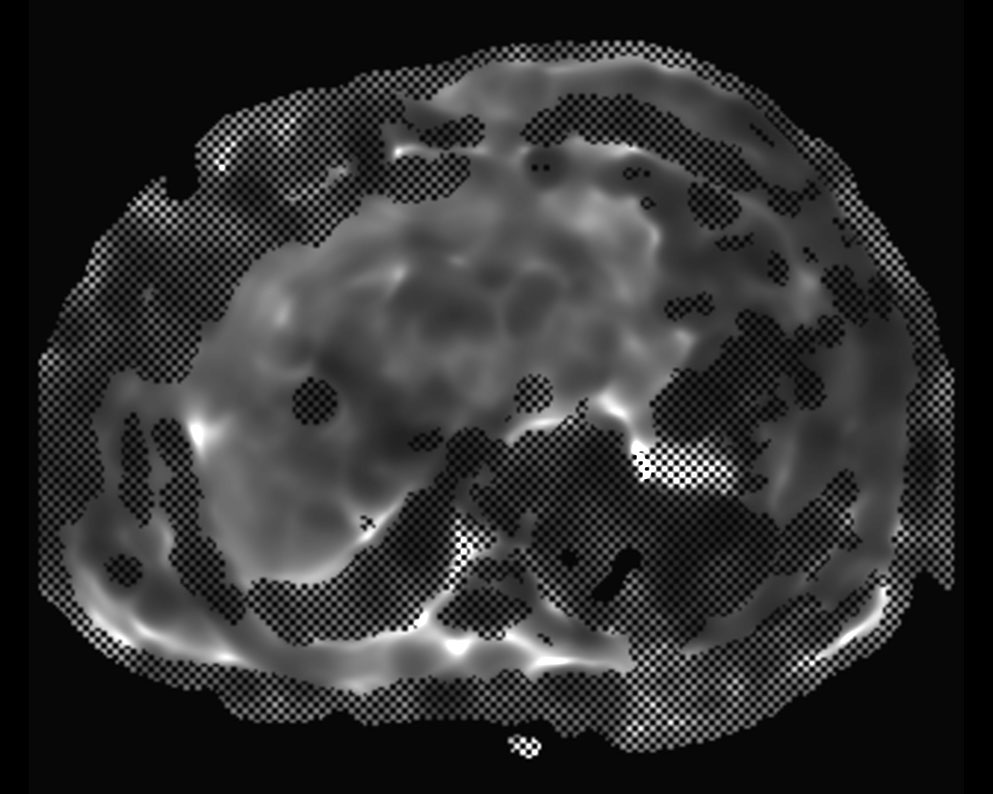

MR Elastography (confidence map) SE-EPI, 13 sec BH/4 slices

MR Elastography (stiffness map) SE-EPI, 13 sec BH/4 slices